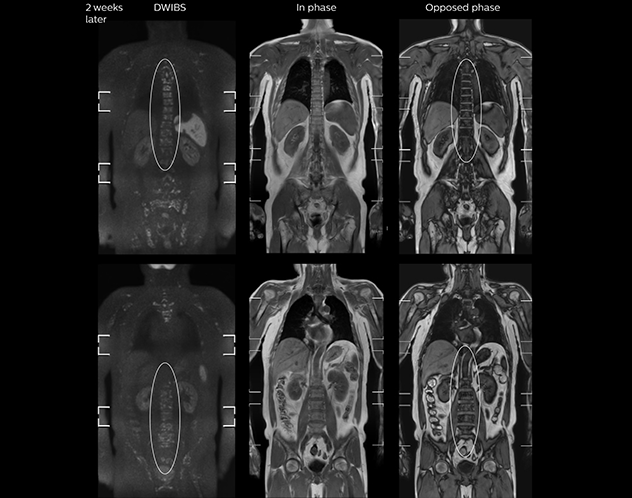

“In-phase and out-phase sagittal T1-weighted FFE images help us to visualize and further characterize bone lesions such as metastasis and bone-marrow hyperplasia that have high signal on DWI. These images are also used throughout radiotherapy, to monitor changes in the fatty bone marrow.”

After implementing the improved whole body protocol, the radiology team initially did not see a large increase in referrals, although Dr. Nobusawa saw clinical cases where the DWIBS images provided him valuable information for diagnosis. This is why Dr. Nobusawa and Mr. Naka started to actively educate referring physicians about the value of whole body DWIBS. They organized several presentations for physicians in the hospital, where they explained how DWIBS can be of value in oncology patients. The information it provides can be useful for physicians when staging cancer, as well as when determining or adjusting treatment strategy. Mr. Naka remembers some cases where DWIBS provided remarkable information. “In one example, DWIBS visualized bone lesions that could not be seen on PET or SPECT. In another case we had found a bone lesion when a normal L-spine scan for narrowing of the disk space was done. One extra DWIBS scan (2 stations, 8 minutes) demonstrated a lesion that later was confirmed to be the primary region of cancer.”

As oncologists and surgeons have learned more about DWIBS, referrals for the exams have increased. In 2015, the 326-bed hospital’s radiology department doubled their number of whole body DWIBS exams compared to 2014.